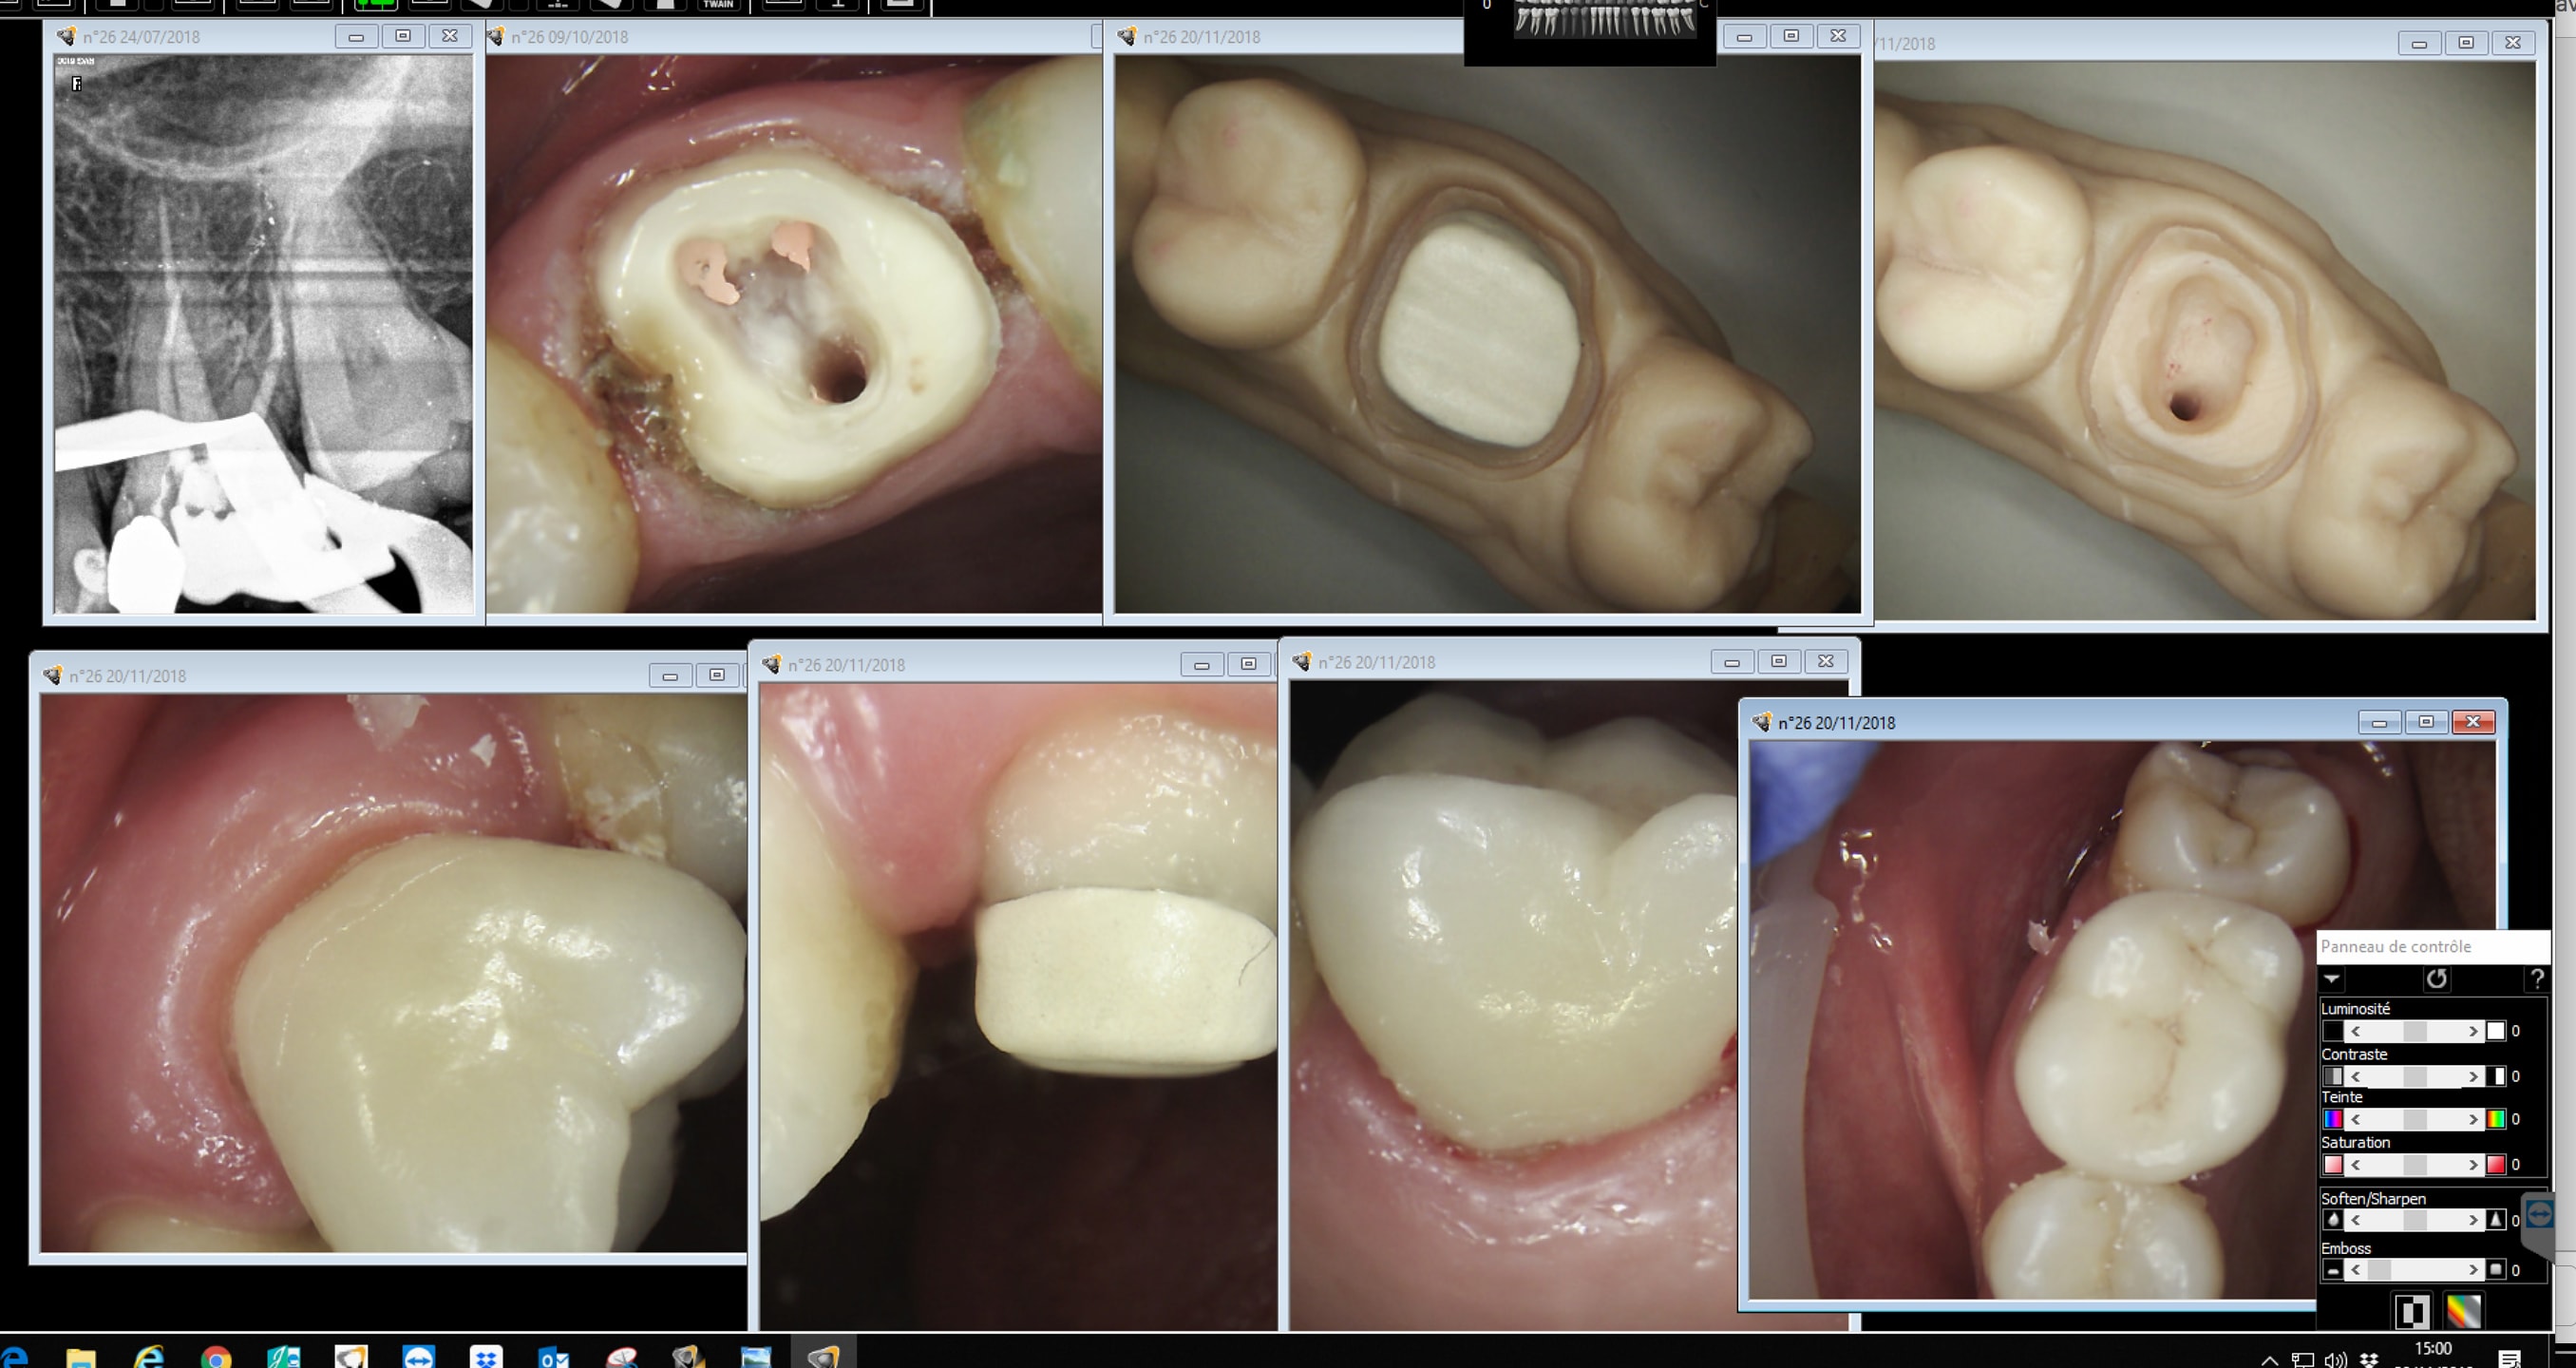

Capture d écran 2018 11 20 15.00 - Eugenol